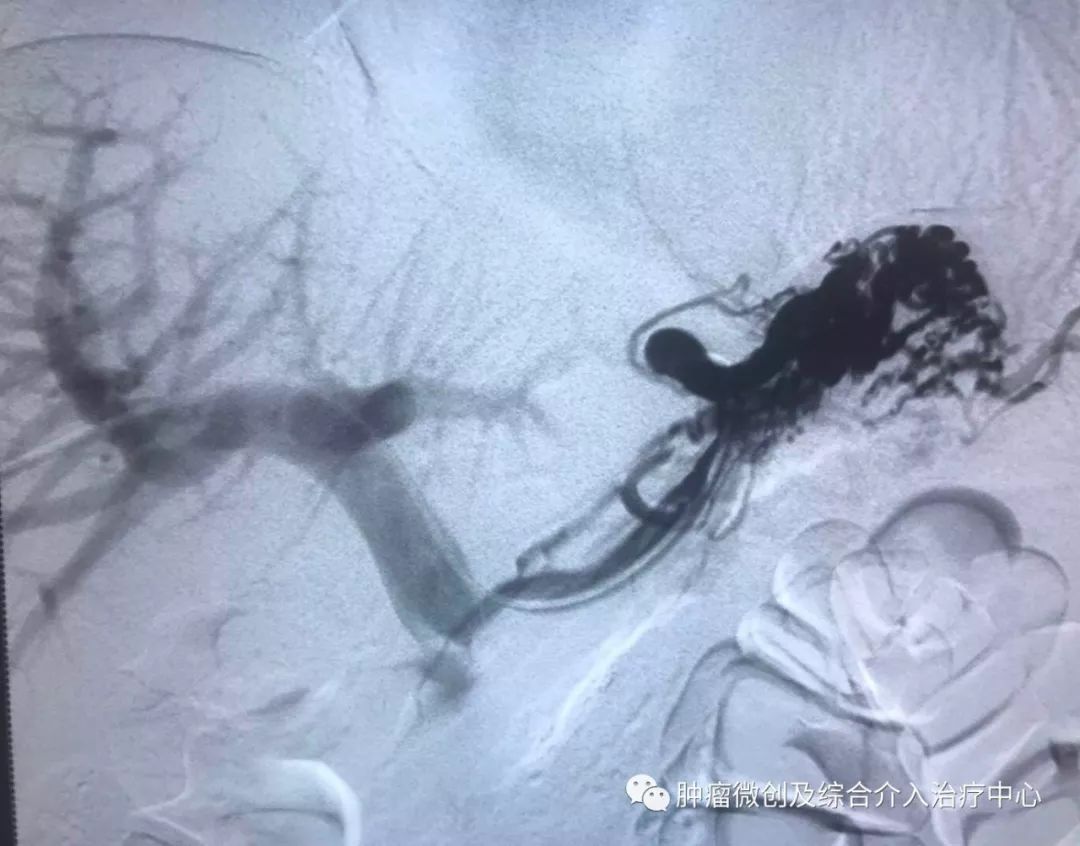

(经皮穿肝-门静脉穿刺成功,门脉高压,门静脉扩张明显)

(食管胃底静脉栓塞术,在血管根部将破裂的上消化道出血血管栓塞完全,即可止血)项目简介:肝硬化门脉高压失代偿期临床表现为反复消化道出血等,患者一般情况欠佳,传统治疗难以改善。食管胃底静脉+胃冠状静脉栓塞术暨经皮肤穿门脉食管胃底+胃冠状静脉栓塞明显降低因消化道大出血导致休克及死亡的风险; 结合内科治疗,其顽固性腹水症状可迅速消退,改善患者生活质量。10肝硬化门脉高压失代偿介入治疗(TIPS术)